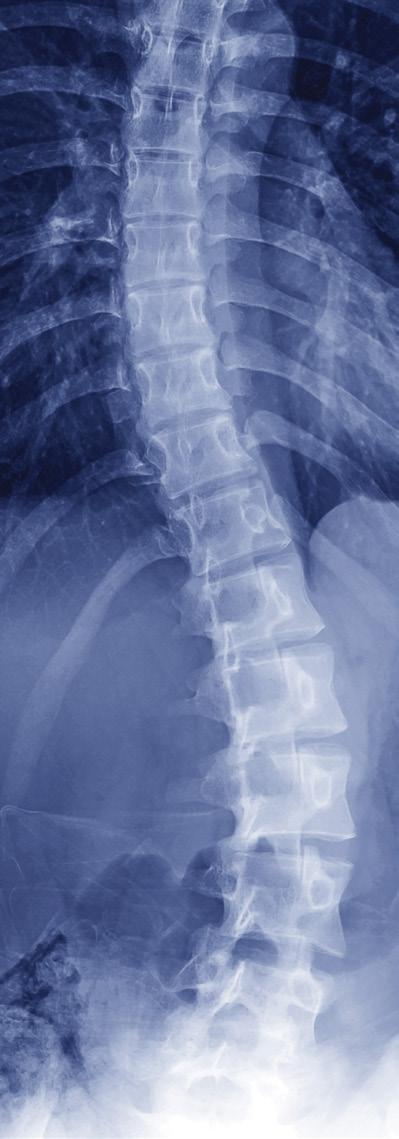

Researchers Leverage AI for Scoliosis Care

A clinical tool that uses artificial intelligence (AI) for Cobb angle measurement is being developed by Yishan Zhong, PhD, from the Georgia Institute of Technology, and spine surgeon Selena Poon, MD, from Shriners Children’s Southern California. They studied the data of 1,000 scoliosis patients to develop an AI model that may be used in the future in patients’ medical records to help inform treatment decisions.

“Current manual scoliosis assessment is timeconsuming for clinicians who are already overwhelmed,” wrote Zhong and Poon. The subjective knowledge and experience of different clinicians result in variation in the measurement.

“Physicians diagnosing scoliosis really use the Cobb angle,” said Fran Farley, MD, Shriners Children’s chief medical officer, adding that AI can be helpful in measuring curves. “This shows lots of potential for minimizing time to make the measurement, but hopefully also making the measurement more accurate.”